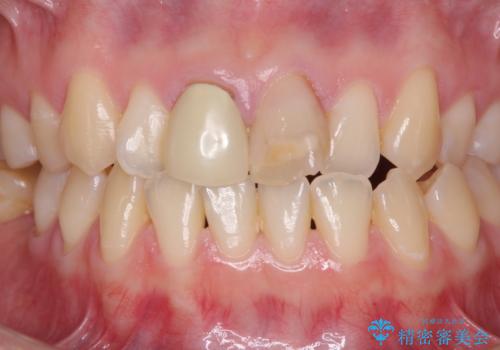

- 前歯の変色が気になるとのことで来院された患者様です。

レントゲン写真より、変色してしまった歯は根管治療がされていなかったため、根管治療後にファイバーコアによる土台築製を行い、前歯2本をオールセラミッククラウンにて補綴することとしました。

変色とともに、捻れていたことも気になっていたので、その両方を解決させることとしました。